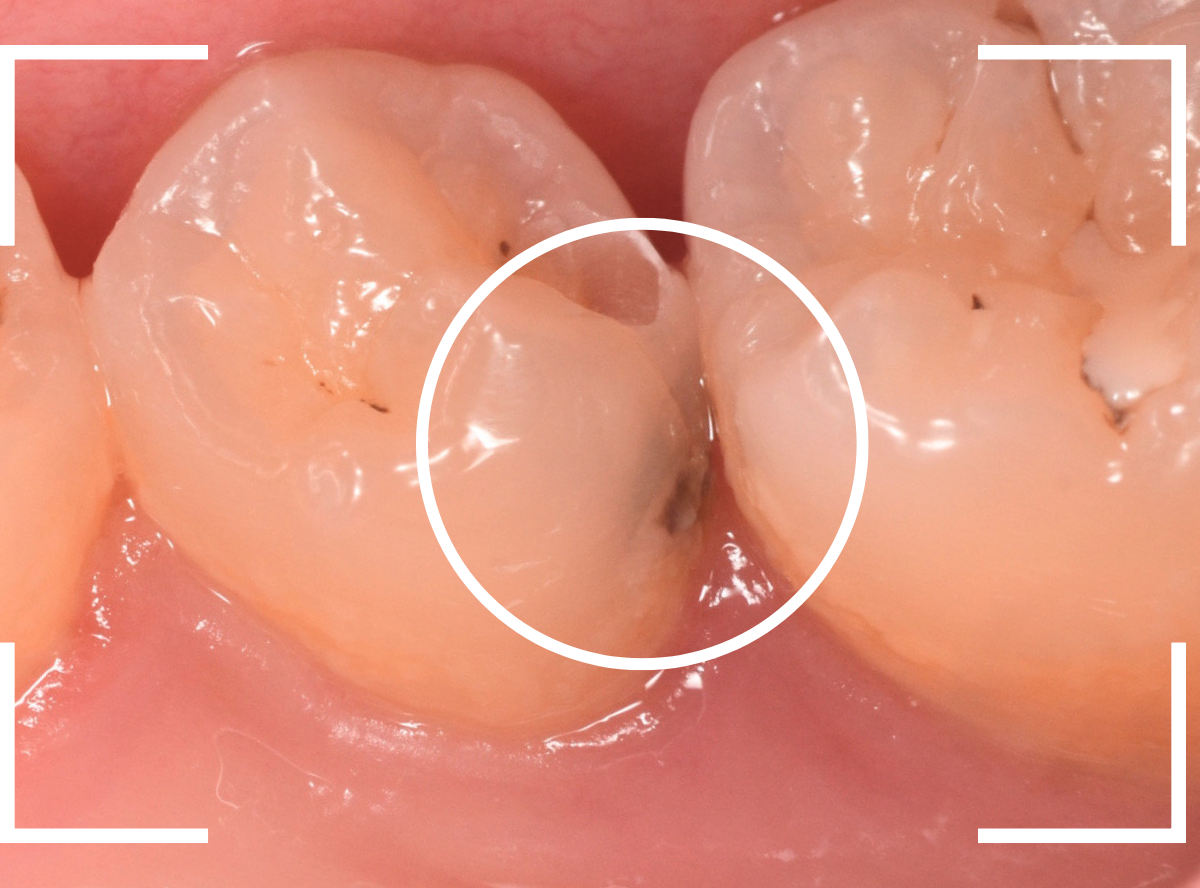

舌のそばの虫歯とセラミック治療

下の奥歯が虫歯になった患者さんのケースです。

〇部が虫歯の部分です。

写真で見てわかるように、常に舌が歯に触っているような状況です。

このような場合、虫歯を見つけづらいですし、治療の難易度もあがります。

虫歯の治療を開始します。

隣の歯とのすき間を中心に広い虫歯になっていました。